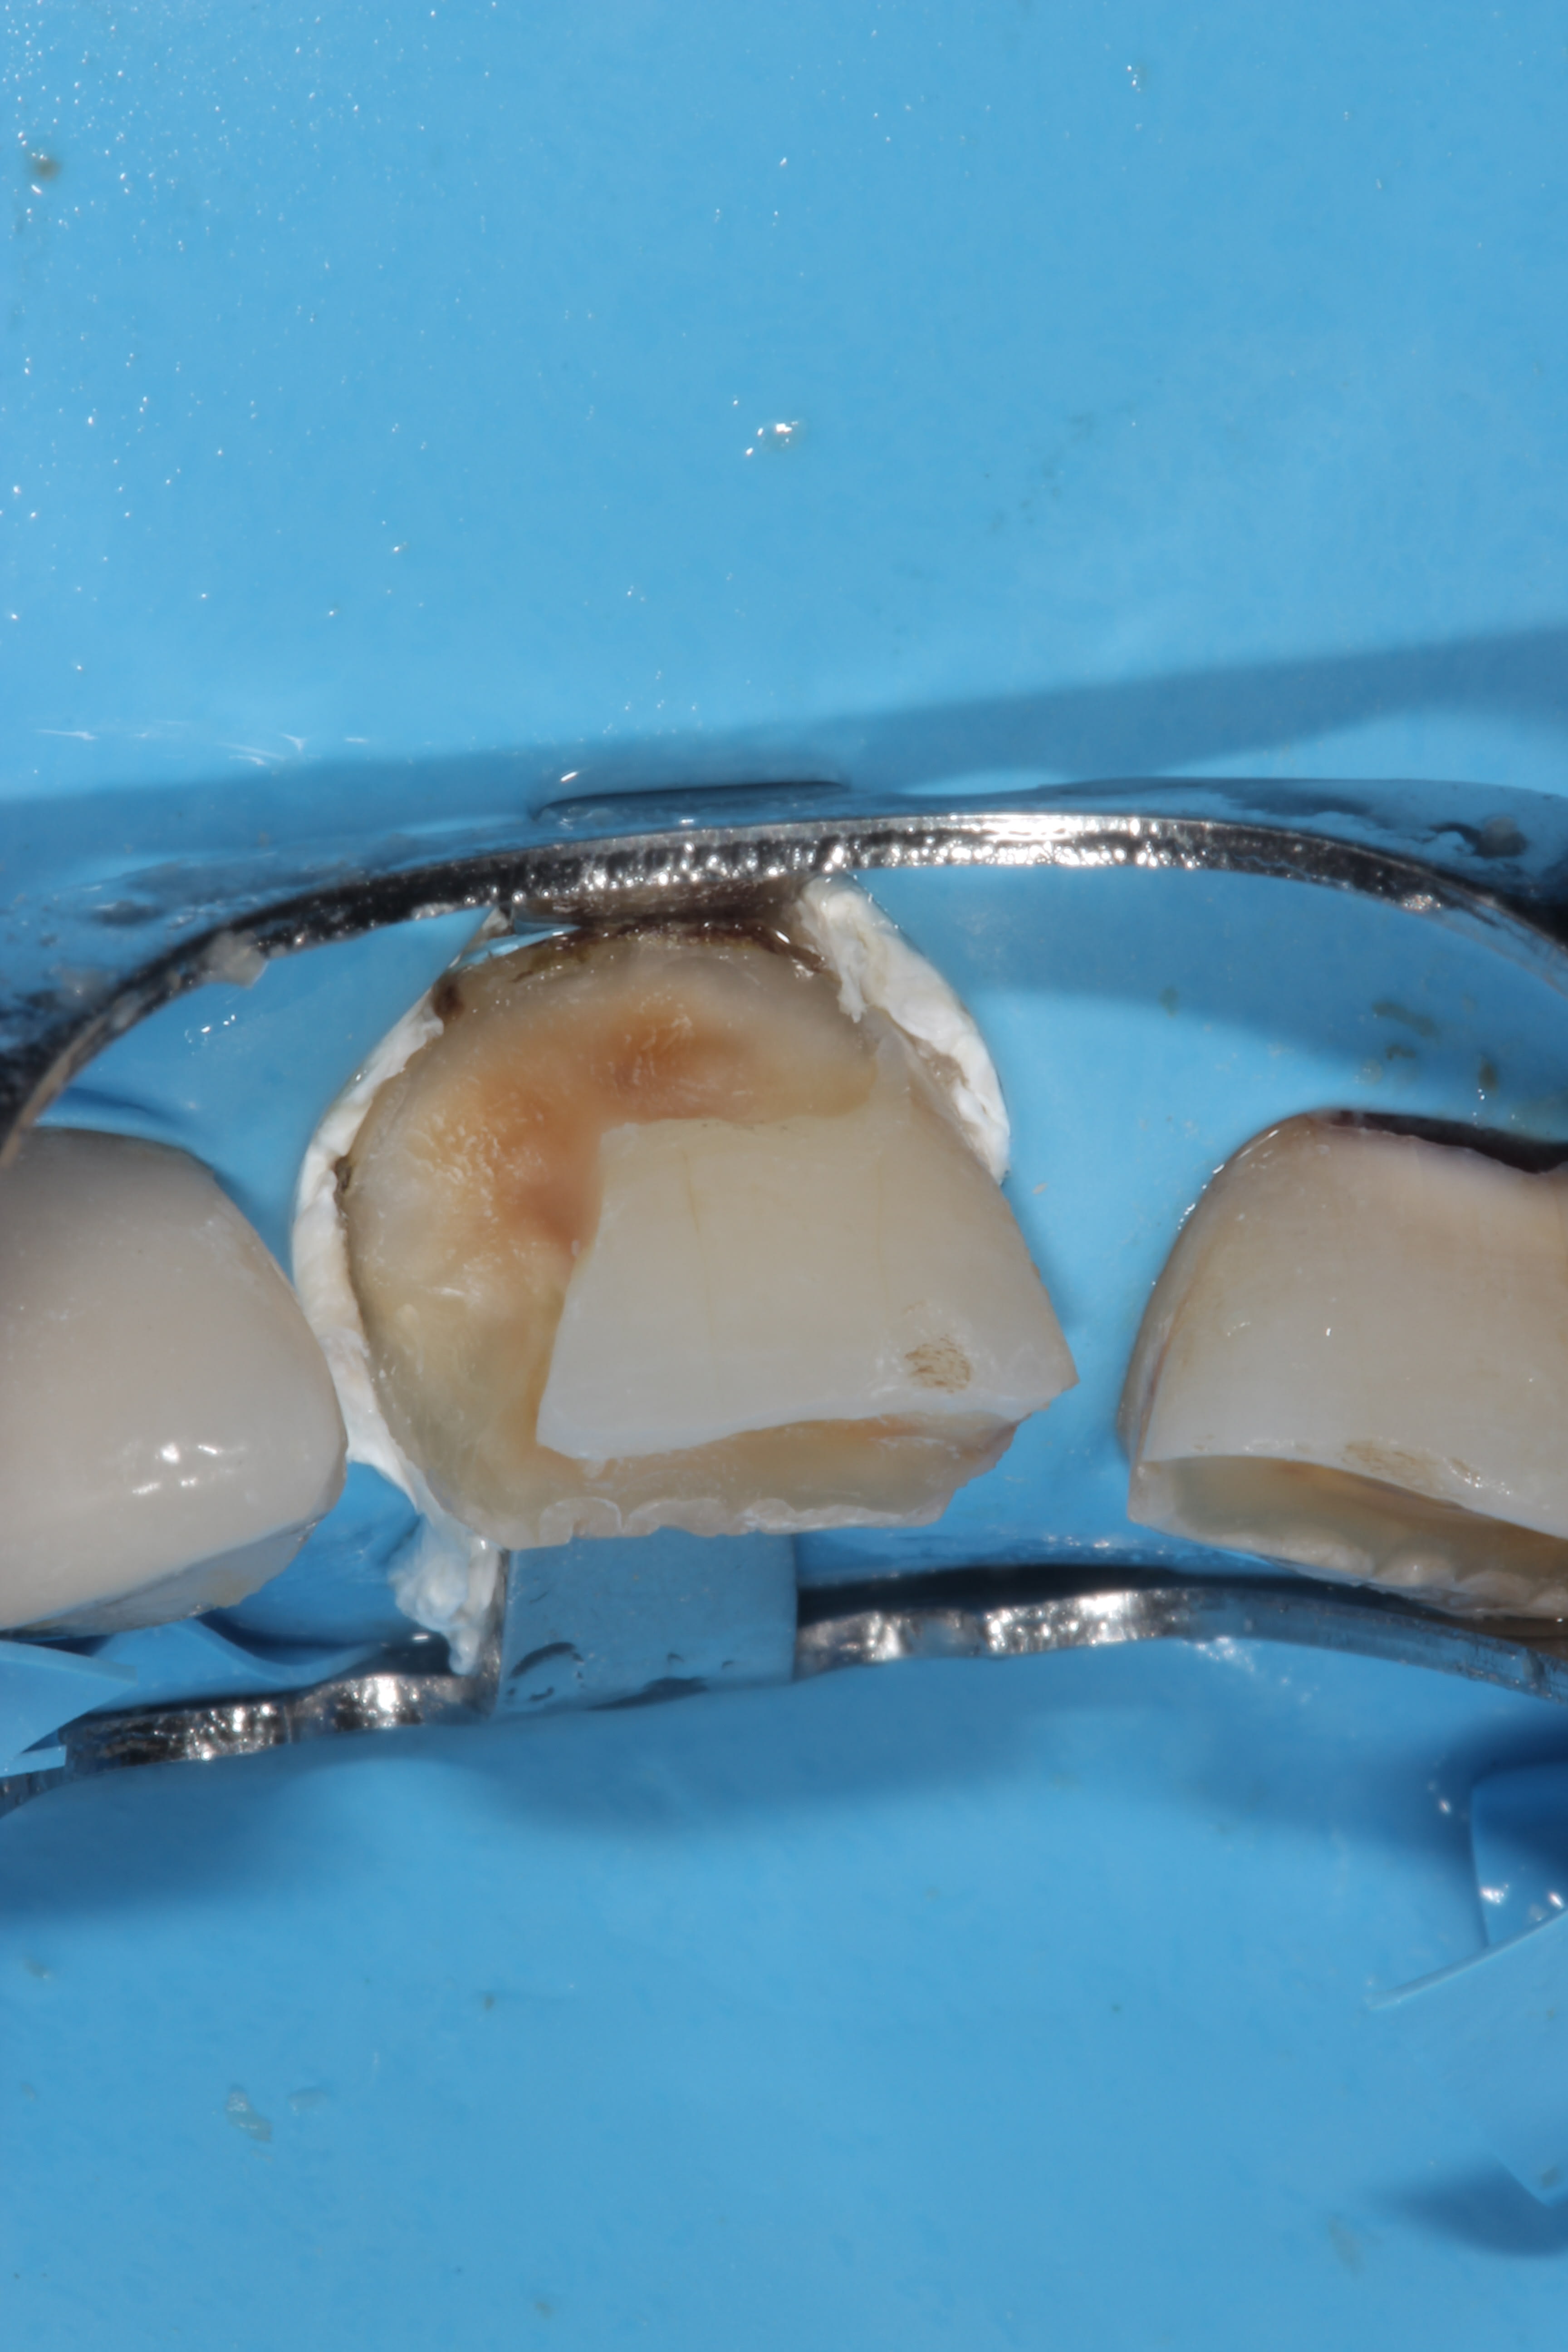

en fait ces caries vont assez profondement et meme s il n' y a pas eu besoin de devitaliser, et le patient n' a plus de symptomes, mecaniquement elles restent fragiles. le collage ne fait pas tout. pour la survie à long terme des dents, couronner me semble le meilleur choix. en plus c' est beaucoup plus simple ( d' un point de vue technique)!

En fait dans le cas de caries profondes en trognon de pomme (tout autour de la dent), faire une couronne (sans tenon, sans inlay core) ne renforce pas du tout la dent : seul le "trognon de pomme" avec un peu de composite collé va servir de soutien à la couronne. A force de choc horizontaux répétés, la couronne va se désolidariser du reste avec du compo et de la dent à l'intérieur...

Dans ce cas là, mieux vaut faire :

- des compo bien réalisés,

- ou dévitaliser et faire RCR+CCM ou IC+CCM

mais compo + CCM = pas bon car tu vas enlever de l'émail et de la dentine saine et fragiliser la dent...

Enlever l' email ne va pas fragiliser la dent. De la dentine oui. C' est la raison pour laquelle je ne fais pas de congé ou autre mais des préparations verticales, pour maintenir de la dentine pericervicale.

Je garde de la ferrule et il devrait pas y avoir de probleme. maintenant, je l' ai déja dit, je n' ai pas une expérience de X0 années . Juste quelques années. Mais dans ma pratique actuelle, c' est ce que je fais. Apres, pour ce qui est des photos avec les cavités, ce ne sont pas les prepas finales, il y a surement eu une reduction des murs fins/fragiles.